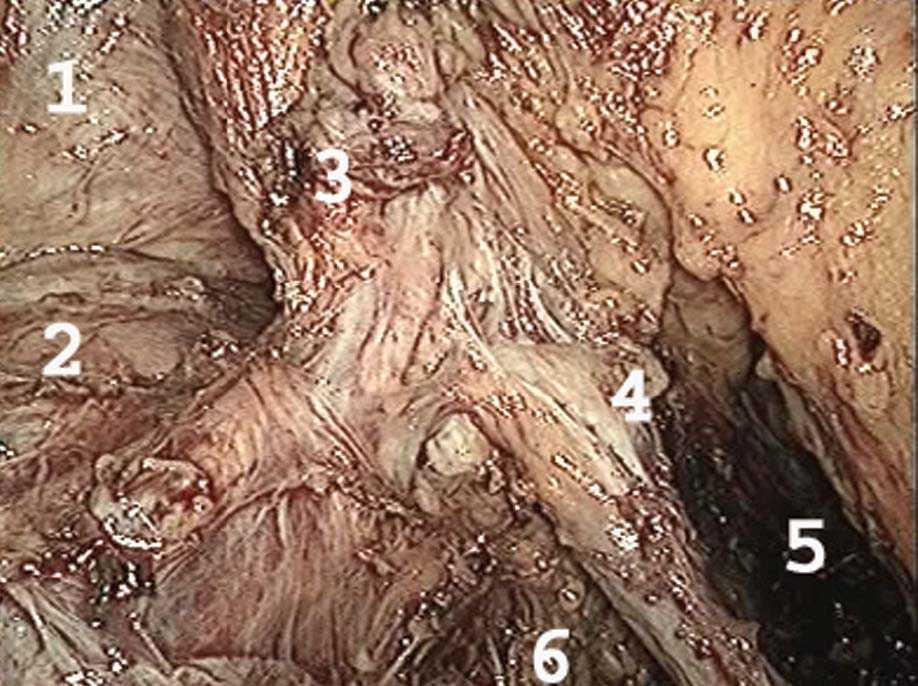

La intervención se inició con la sección distal de los ligamentos redondos y el desarrollo de las fosas paravesicales hasta la fascia endopélvica y una linfadenectomía pélvica bilateral hasta la bifurcación de la arteria ilíaca primitiva. Los ganglios se depositaron en una endobolsa que se extrajo por vía vaginal al finalizar la intervención. Seguidamente, se realizó la exposición de la fosa pararrectal hasta el músculo elevador del ano (fig. 2). En los últimos 14 casos se ha realizado la disección de los nervios esplánicos, situados en la cara posteroinferior del parametrio, para preservar la inervación parasimpática del recto y la vejiga (fig. 3). A continuación se realizó la sección de la arteria uterina en su origen y la resección radical del parametrio con una pinza bipolar (Ligasure) o bisturí armónico (ultracisión) hasta los nervios esplánicos, previamente expuestos (fig. 4). En los primeros casos la resección del parametrio se realizó en bloque utilizando endocortadoras mecánicas y, más tarde, el Ligasure de 10 mm (Atlas, Tyco). A medida que se adquirió experiencia, se profundizó en la disección de las estructuras anatómicas del parametrio, lo que posibilitó la sección individualizada de estas estructuras que comprenden, en sentido descendente, arteria uterina, venas uterinas, venas de drenaje vesicouterinas y arteria rectal media. La hemostasia y la sección se realizaron con instrumental de 5 mm (Ligasure o ultracisión).

Figura 3.Detalle de las raíces nerviosas una vez seccionado el parametrio: útero (1); recto (2); fosa paravesical (3); fosa pararrectal (4); pared pélvica (5), y líneas de sección parametrial (6).

Figura 4.Detalle del ligamento uterosacro izquierdo: cara posterior del cérvix (1); uréter (2); hoja externa del ligamento uterosacro, que contiene el plexo hipogástrico inferior (3); espacio rectovaginal (4); hoja interna del ligamento uterosacro que se resecará (5), y cara anterior del recto (6).